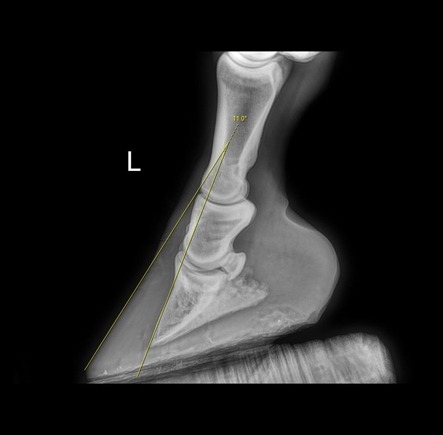

Extreme neglect of the feet, which leads to the toe becoming very long and slipper-like, puts excessive stress on the laminae (picture pulling a really long fingernail away from its bed), and some degree of laminitis is inevitable. Sometimes, careful farriery can rectify the situation, but this will depend on how severe the damage is. X-rays will be invaluable in assessing this. Most of the cases that I see like this are presented to me by a welfare organisation, rather than by an owner.